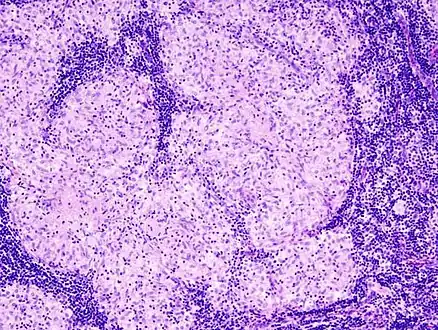

Histopathology

Sarcoidosis is characterized by the formation of non-necrotizing ("non-caseating") granulomas in various organs and tissues.[96] Giant cells, specifically Langhans giant cells, are often seen in sarcoidosis.[97] Schaumann bodies seen in sarcoidosis are calcium and protein inclusions inside of giant cells as part of a granuloma.[98] Asteroid bodies can be seen in sarcoidosis.[98] Hamazaki–Wesenberg bodies can be seen in lymph nodes and more rarely in lung biopsies with sarcoidosis and are inclusion bodies of lysosomes with protein, glycoprotein and iron.[99]

Sarcoidosis in a lymph node